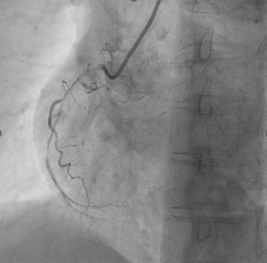

Pre-dilationwith 1.5x15mm compliant balloon. (Balloon didn’t go beyond this point).Changed to workhorse wire insidemicrocatheter by trapping the wire. Coronary dissection NHLBI- Type D/F seenwith reduced antegrade flow

Pre-dilationwith 1.5x15mm compliant balloon. (Balloon didn’t go beyond this point).Changed to workhorse wire insidemicrocatheter by trapping the wire. Coronary dissection NHLBI- Type D/F seenwith reduced antegrade flow